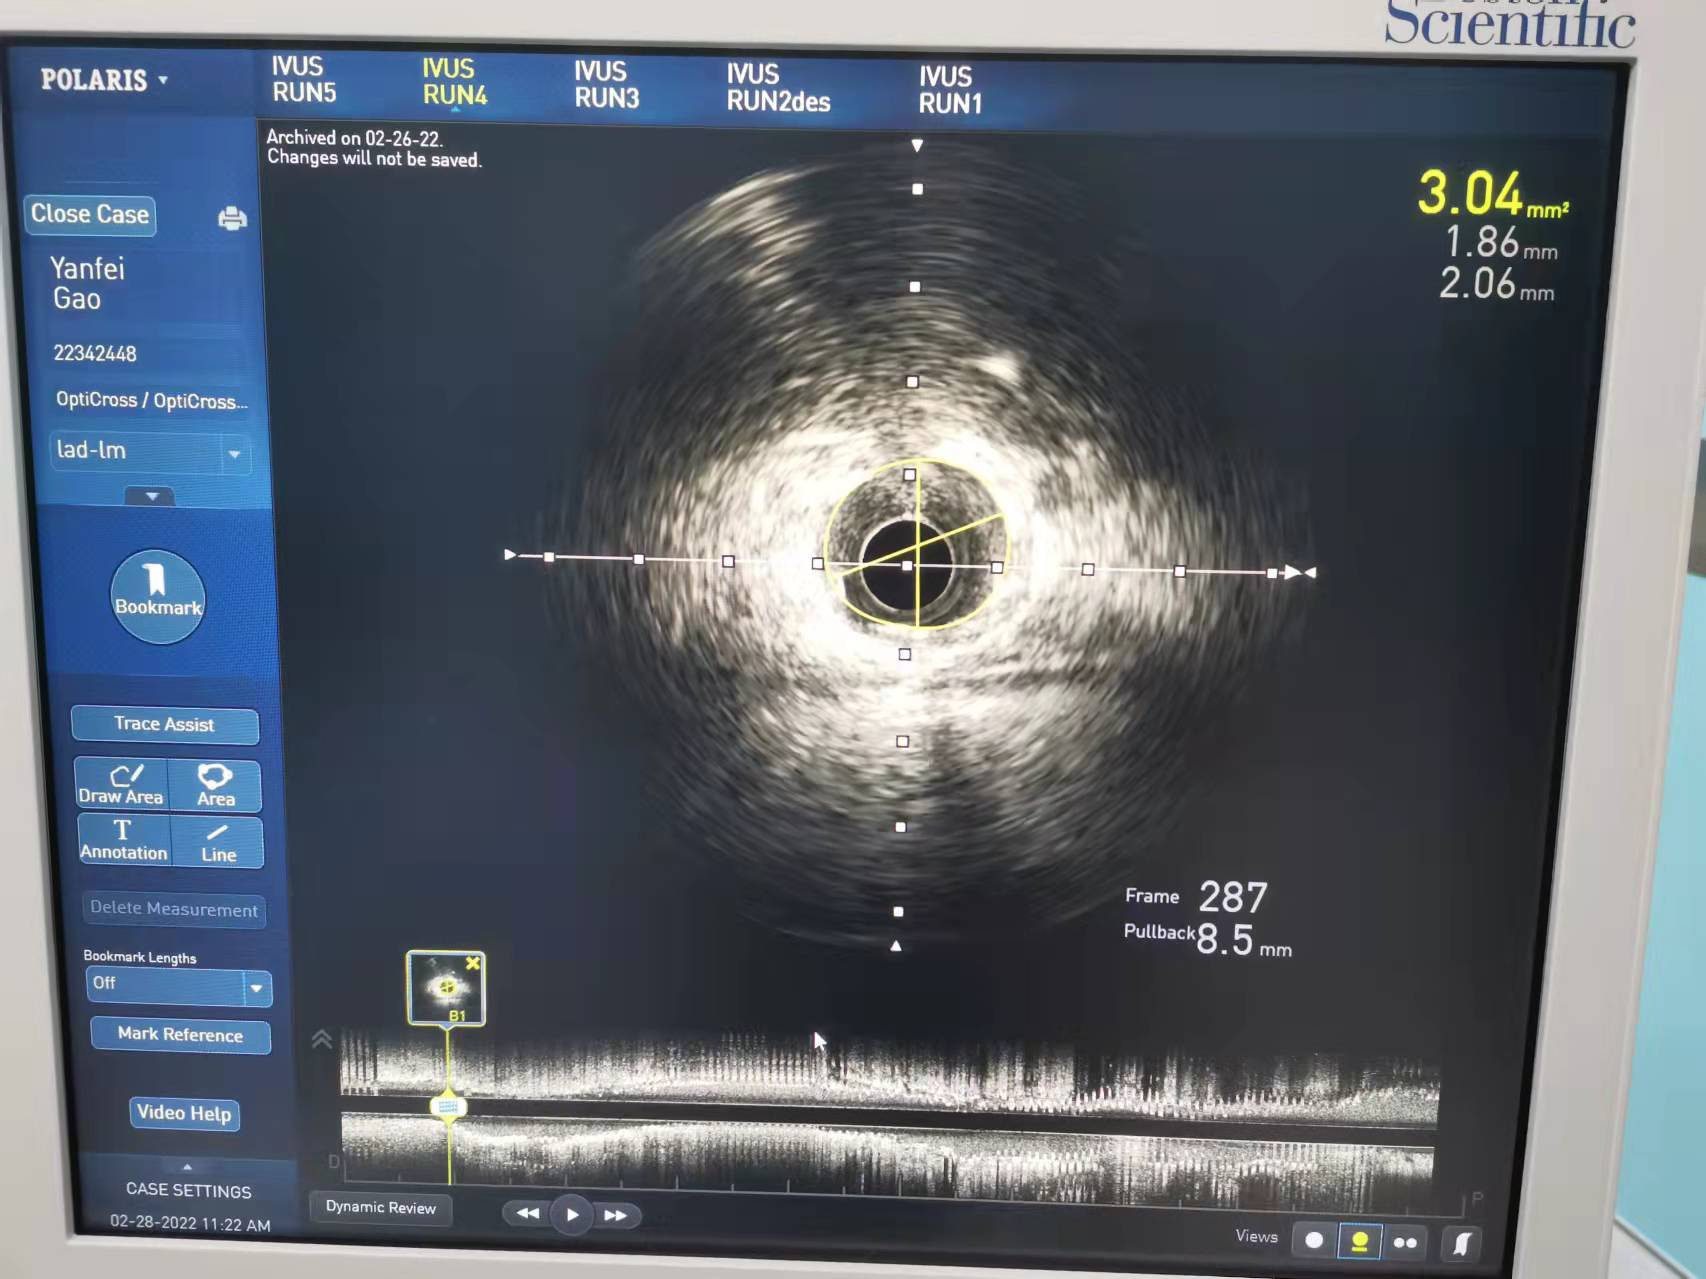

冠脉支架术后病变近端管腔面积8.59mm2

冠脉支架术后病变远端管腔面积3.04mm2